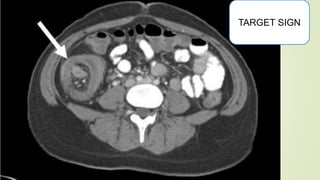

TARGET SIGN

CLINICAL FEATURES  Intermittentpain  Red currant jelly stool  O/E :-  right iliac fossa empty (Dance sign)  Sausage or banana shaped lump with concavity towards umbilicus